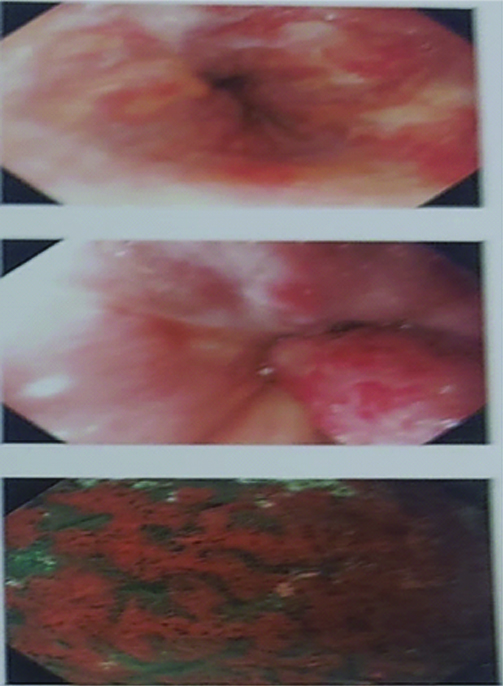

Based on the triad of RA with neutropenia and splenomegaly, she was diagnosed with Felty syndrome and portal hypertension. In light of the ongoing Upper Gastrointestinal (UGI) bleed, she was initially resuscitated, after which she underwent an upper Gastroinstestinal Tract (GI) endoscopy. The endoscopy revealed grade II varices in three locations, characterised by red colour spots/signs [Table/Fig-7]. Endoscopic variceal ligation was performed.

UGI endoscopy showing grade II varices in three locations with red colour spot sign.

The repeat upper GI endoscopy after six months revealed grade III oesophageal varices [Table/Fig-8], along with severe portal gastropathy and duodenopathy, with no fresh episodes of bleeding.

UGI endoscopy showing grade III oesophageal varices with post Endoscopic Variceal Ligation (EVL) scarring with severe portal gastropathy and duodenopathy.

Case series on Felty syndrome in the past have reported the presence of portal hypertension resulting from idiopathic non cirrhotic portal hypertension (which includes nodular regenerative hyperplasia), with episodes leading to variceal bleeding [Table/Fig-9] [12,13]. About 20% of patients with Felty syndrome showed portal hypertension and/or bleeding oesophageal varices [14]. The mechanism of portal hypertension is partly due to increased splenic blood flow and partly due to sinusoidal resistance. The latter occurs due to compression of intrahepatic venous radicles or the presence of microthrombi. In a series of cases, it was reported that an increase in splenic blood flow was attributed as the cause of portal hypertension [15].